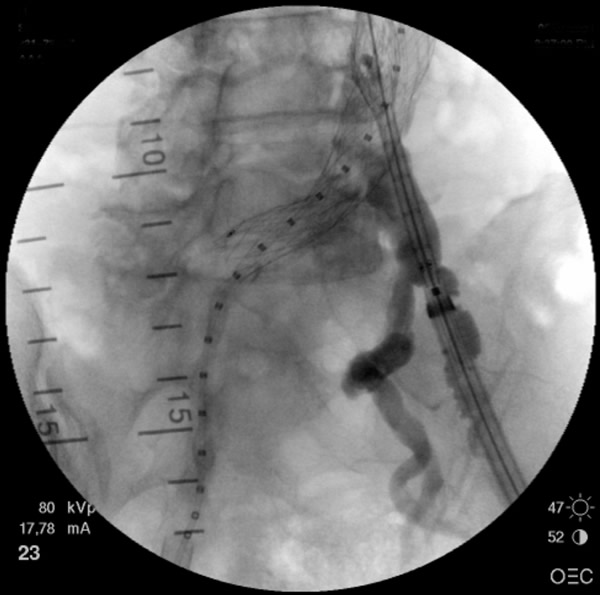

Figure 4: Deployment of contralateral limb. Angiogram reveals the location of the internal iliac artery.

- After the deployment of the contralateral iliac limb (Figure 4), the surgeon will evaluate the need for further iliac limb extenders or aortic cuffs. It is important to cover the entire length between the lowest renal artery and the internal iliac artery. The stent grafts are subsequently ballooned as suggested by the IFU. An IVUS interrogation of the entire stent graft and surrounding aortic branches is performed. This will detect any circumferential stent mal-apposition to the proximal or distal landing zone that may lead to endoleak. A completion angiogram is performed to confirm lack of gross endoleak (Figure 5, Video 1, , “Completion angiogram” confirms the patency of both renal arteries and lack of proximal endoleak (type Ia).) However a single aortogram may miss endoleak due to projection overlap. A bi-plane aortogram is more reliable in excluding any significant procedural endoleak.